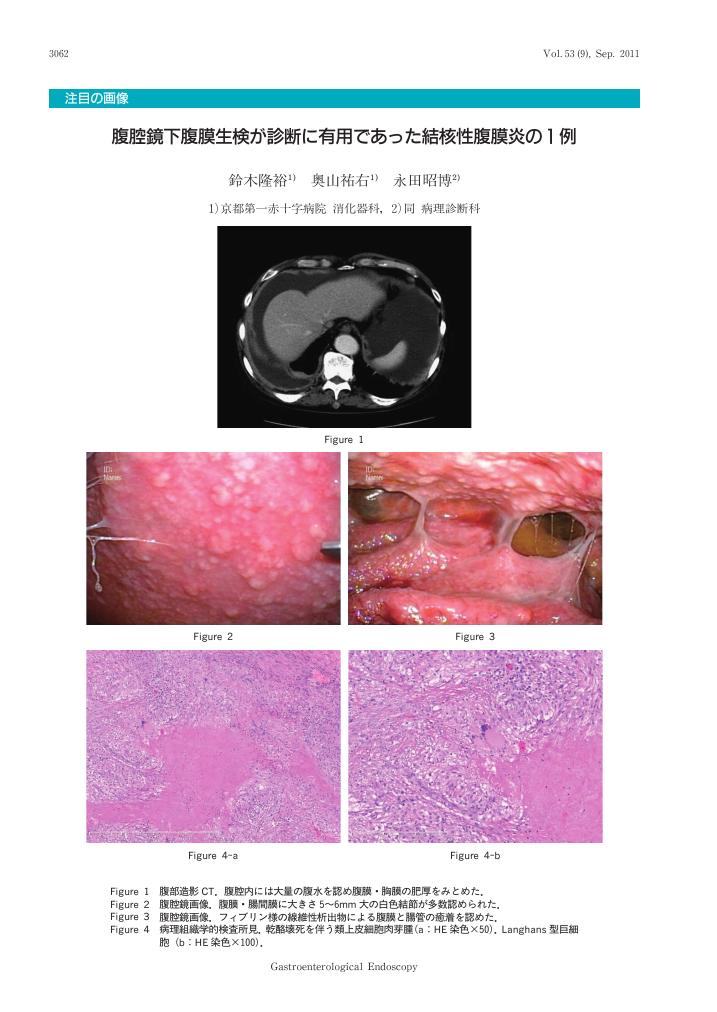

腹腔鏡下腹膜生検が診断に有用であった結核性腹膜炎の1例